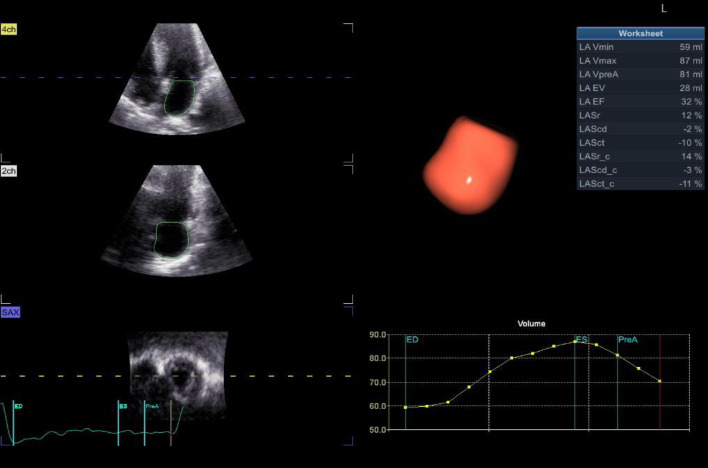

Results: By 2D echocardiography, patient group revealed significantly lower all LA functions vs. control group including reservoir (26 ± 4 vs. 43 ± 3, P < 0.001), conduit (-14 ± 2 vs. -25 ± 2, P < 0.001), and booster pump functions (-12 ± 2 vs. -18 ± 1, P < 0.001). PAP was significantly higher in patient group (42 ± 7 vs. 27 ± 4 in control group). LVGLS was significantly lower in patient group (-15±1.4% vs. -23±2% in control group). Using 3D speckle tracking echocardiography (STE), there were a significantly higher indexed maximum LA volume (Vmax indexed) (43.5 ± 5.6 vs. 28.7 ± 3.7, P < 0.001), but significantly lower left atrial strain at reservoir function (LASr) (24 ± 4 vs. 41 ± 3, P < 0.001), left atrial strain at conduit function (LAScd) (-13 ± 2 vs. -24 ± 2, P < 0.001), and left atrial strain at contractile function (LASct) (-11 ± 2 vs. -18 ± 1, P < 0.001).

Abstract Image